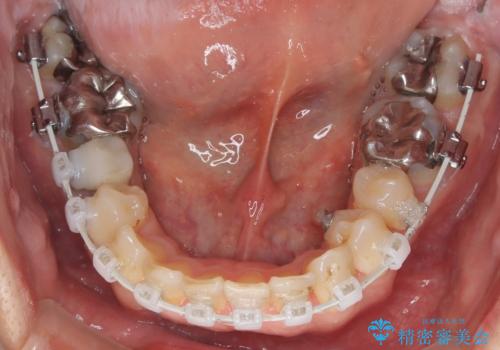

- 矯正装置

- 審美装置

上顎はリンガルアーチにて遠心移動を行うことで前歯を唇側傾斜させずに配列することができました。